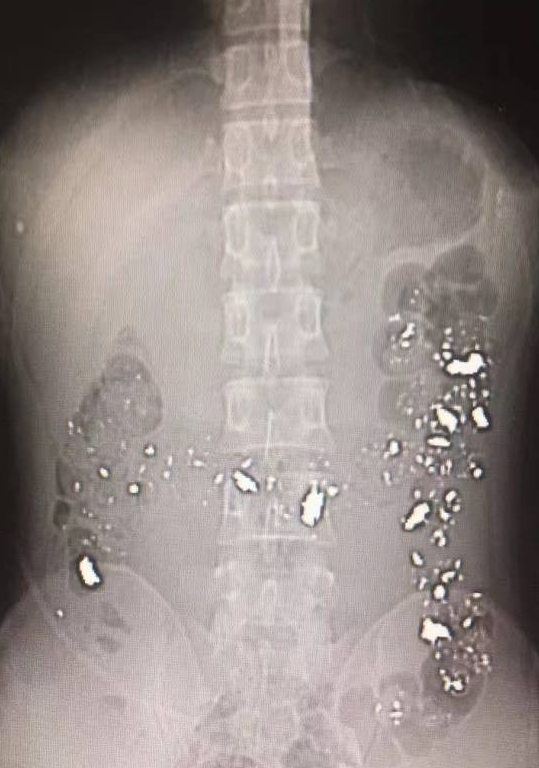

检查结果一出来,所有人都惊呆了!!!

他一肚子都是亮闪闪的金属!!!

以下腹部CT片

黄桔秀拿着CT片来到小伙子床边,小伙子这才说出实情——他食铅已经一年了!

“铅会对血液系统造成严重损害,难怪他贫血这么严重!"黄桔秀说,这下之前的疑问都得到了解答。